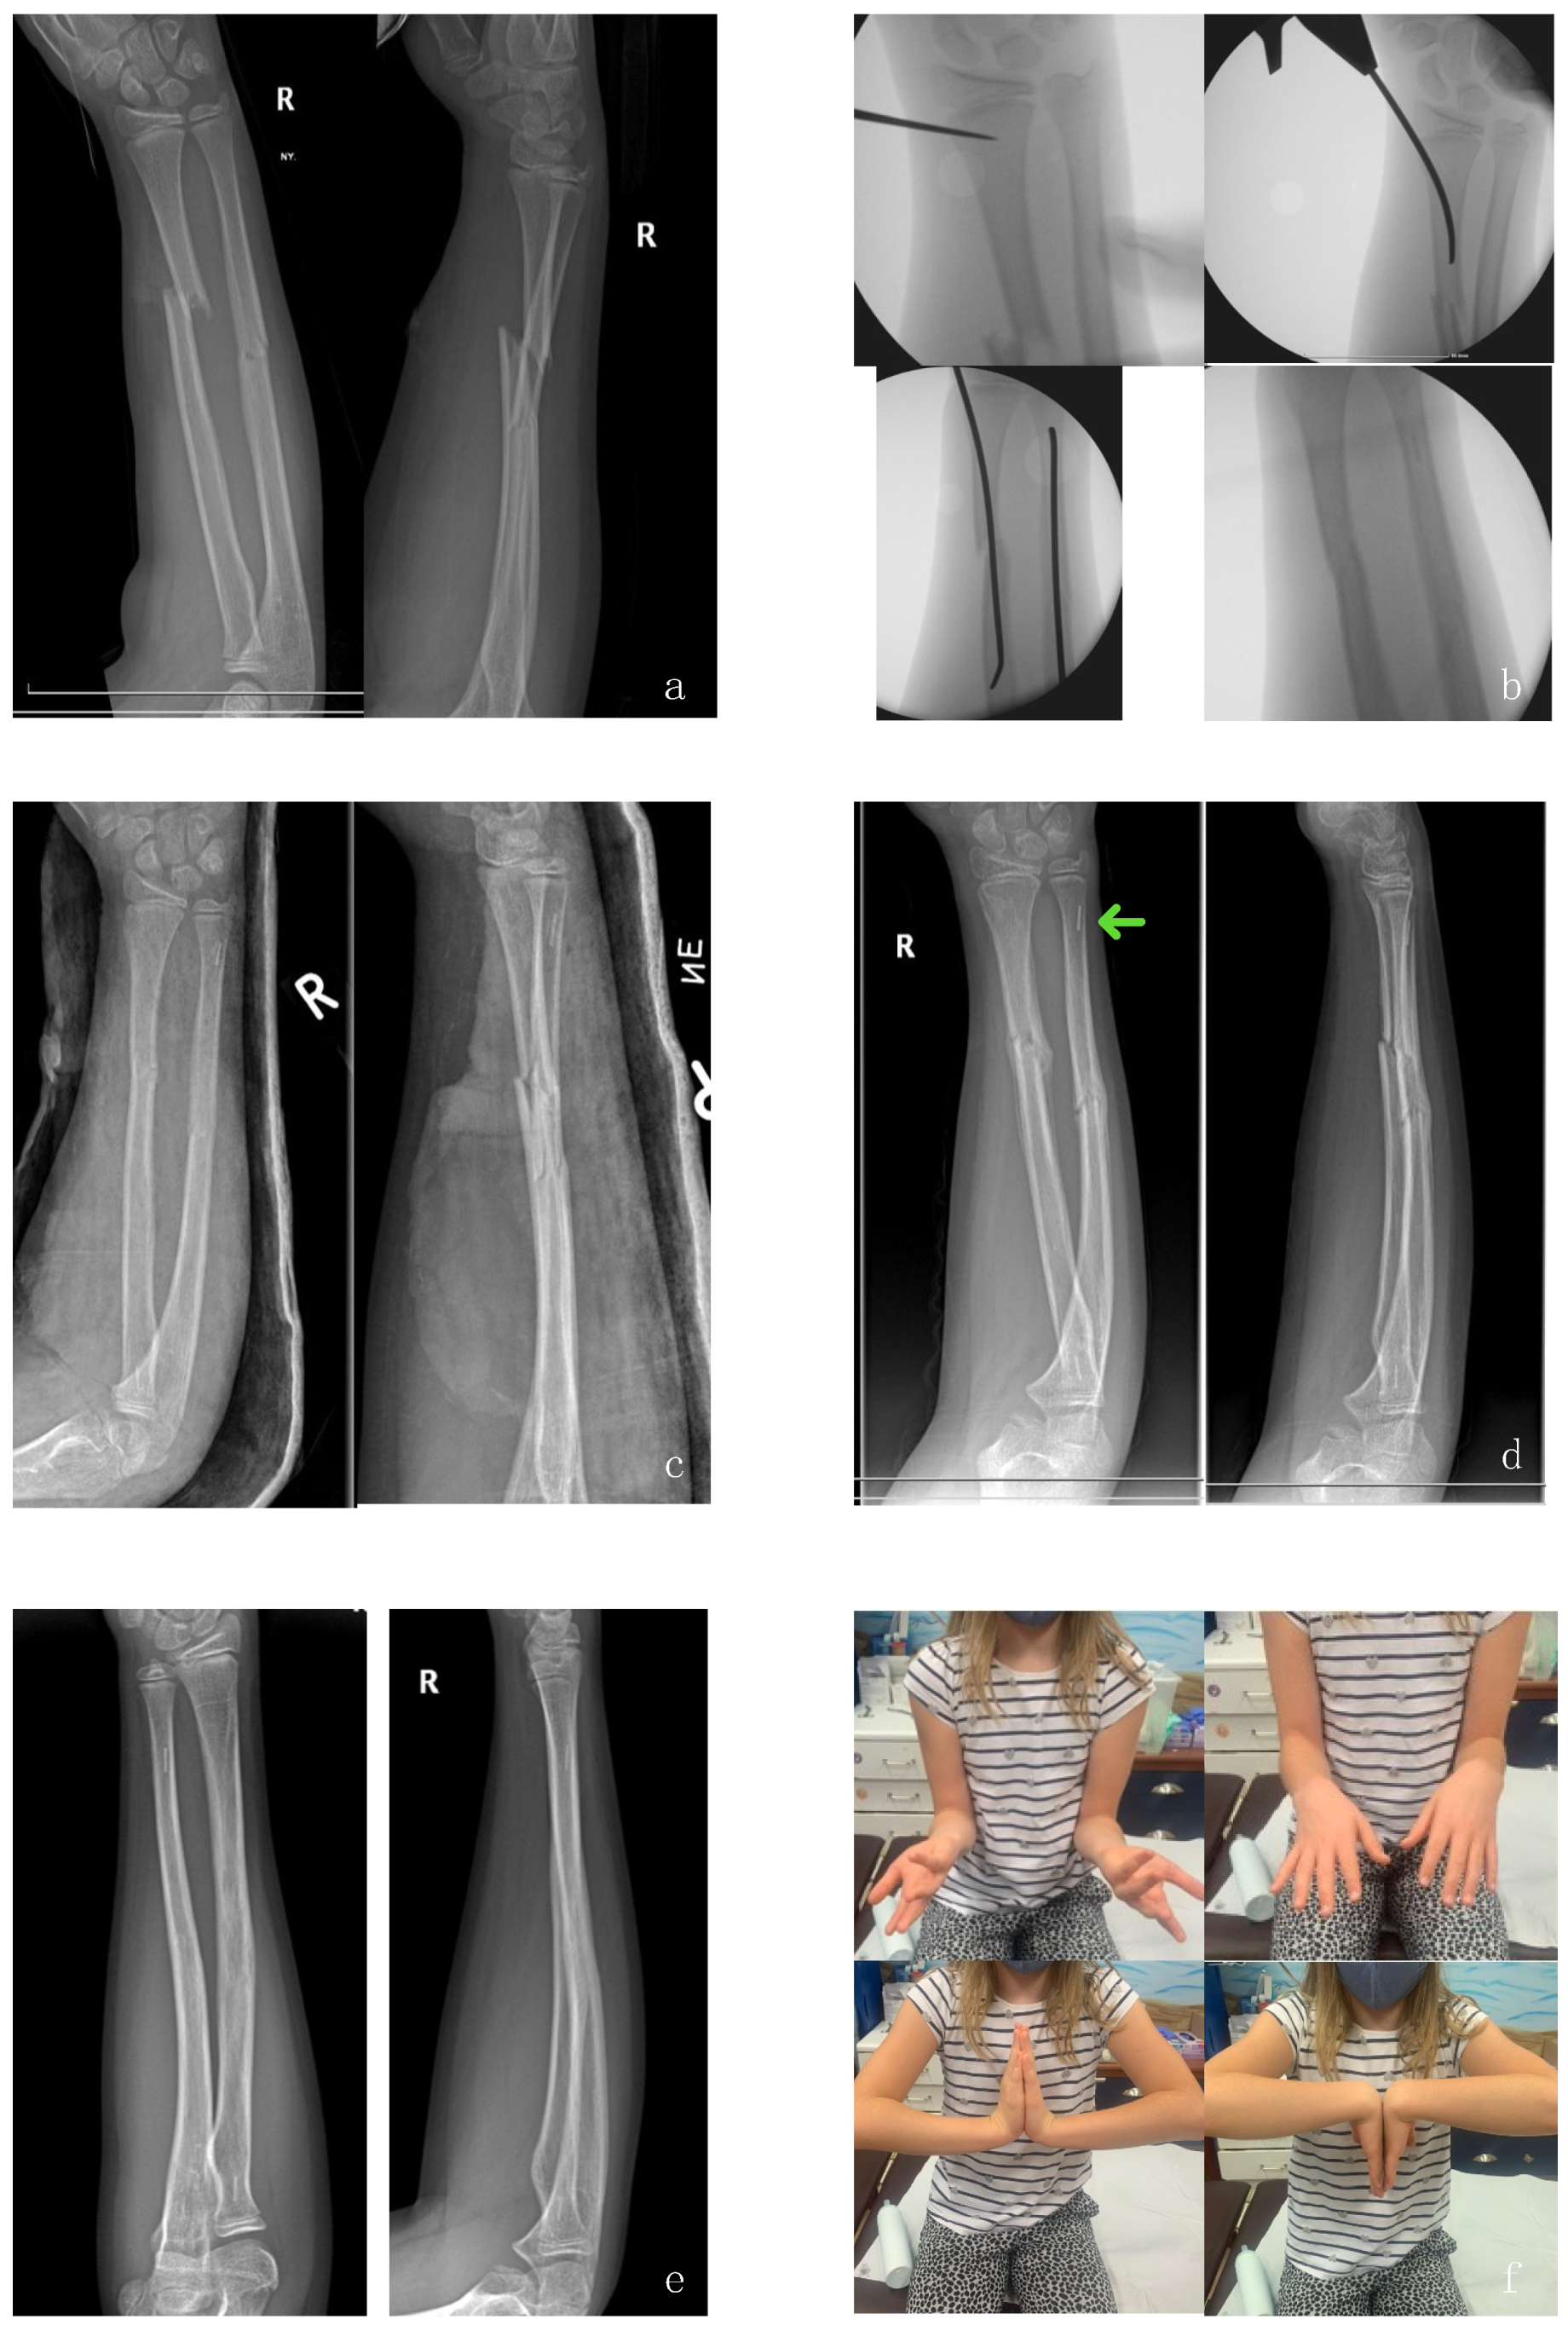

3. Operative Technique and Preliminary Results

3.1. Preliminary Results (Pilot Study)

3.1.2. Refracture